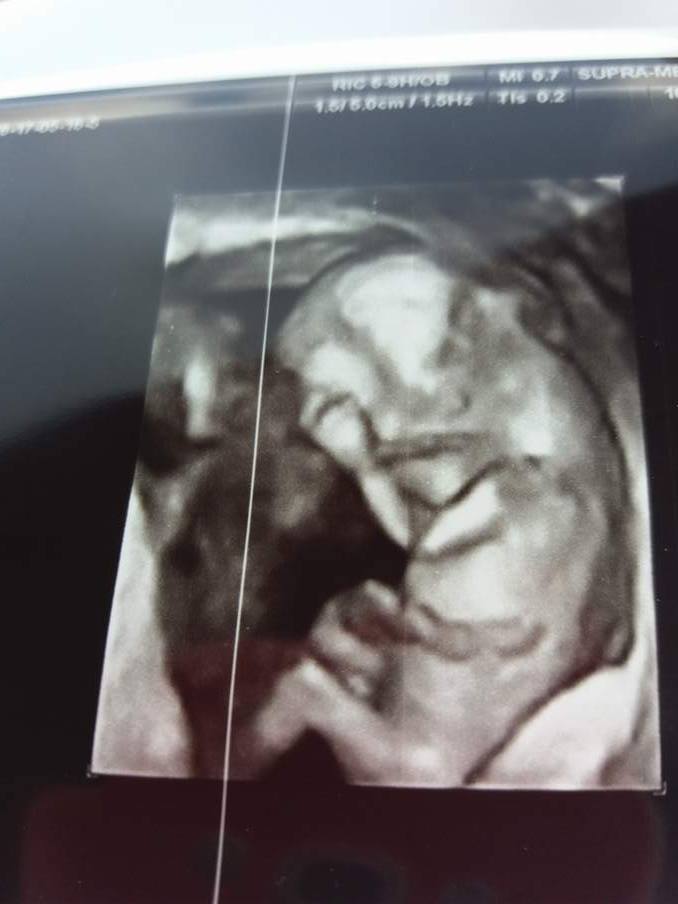

Ja już po prenatalnych :) Wszystko jest dobrze :) Dzidziuś ma 5 cm . Lekarz obstawia na 80 % dziewczynkę

Ja juz po wizycie:) maleńkie zdrowe, ruszało sie, jedno ujęcie na monitorze było tak bardzo widoczne ze miałam wrażenie ze widze całego bobaska z rączkami, nóżkami, noskiem, oczkami i usteczkami:) niestety zdjecie juz nie jest takie wyraźne. W 3 tyg maluszek urósł 2 cm, ma teraz 4,16cm:) według ostatniego usg dzis powinno byc 10tc i 4 dni, a według dzisiejszego 11 tydz i 1 dzien , czyli data porodu znowu mi sie zmieniła na 4 grudnia .